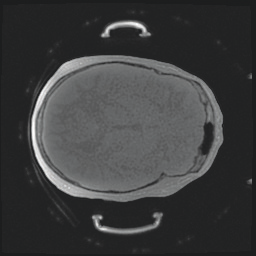

Model-based treatment planning for transcranial ultrasound therapy typically involves mapping the acoustic properties of the skull from an x-ray computed tomography (CT) image of the head. Here, three methods for generating pseudo-CT images from magnetic resonance (MR) images were compared as an alternative to CT. A convolutional neural network (U-Net) was trained on paired MR-CT images to generate pseudo-CT images from either T1-weighted or zero-echo time (ZTE) MR images (denoted tCT and zCT, respectively). A direct mapping from ZTE to pseudo-CT was also implemented (denoted cCT). When comparing the pseudo-CT and ground truth CT images for the test set, the mean absolute error was 133, 83, and 145 Hounsfield units (HU) across the whole head, and 398, 222, and 336 HU within the skull for the tCT, zCT, and cCT images, respectively. Ultrasound simulations were also performed using the generated pseudo-CT images and compared to simulations based on CT. An annular array transducer was used targeting the visual or motor cortex. The mean differences in the simulated focal pressure, focal position, and focal volume were 9.9%, 1.5 mm, and 15.1% for simulations based on the tCT images, 5.7%, 0.6 mm, and 5.7% for the zCT, and 6.7%, 0.9 mm, and 12.1% for the cCT. The improved results for images mapped from ZTE highlight the advantage of using imaging sequences which improve contrast of the skull bone. Overall, these results demonstrate that acoustic simulations based on MR images can give comparable accuracy to those based on CT.